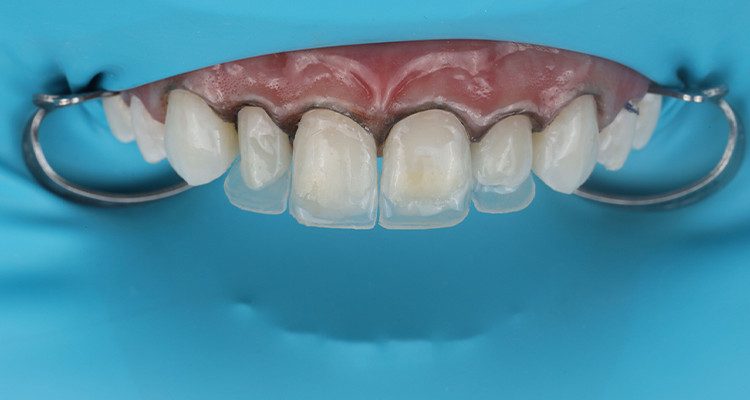

2 | Aspecto após a remoção parcial das resinas prévias.

Ao decidir manter a resina de restaurações pré-existentes, alguns pontos devem ser levados em consideração, como visualização das margens bem definidas e ausência de manchamentos ou infiltrações. Esse processo de reparo é considerado a alternativa mais conservadora por evitar maior desgaste de superfície dentária. Se houver dúvida quanto a esses aspectos, a remoção total é indicada.